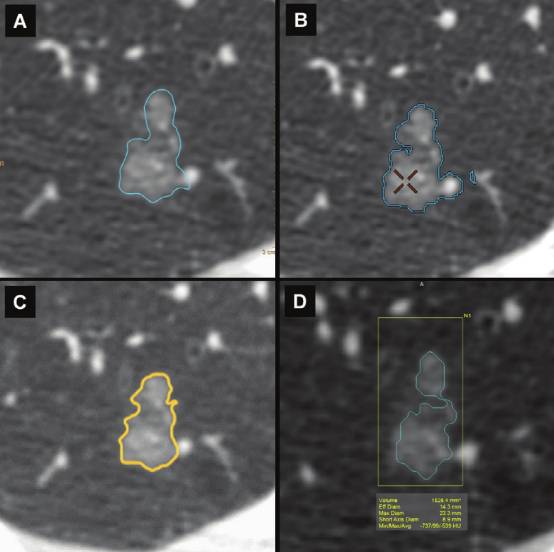

四个不同软件对磨玻璃结节的分割和体积分析。计算的结节体积为A、2019 mm3,B、2059 mm3,C、1949 mm3,D、1528 mm3,导致测量之间的最大差值为531 mm3。